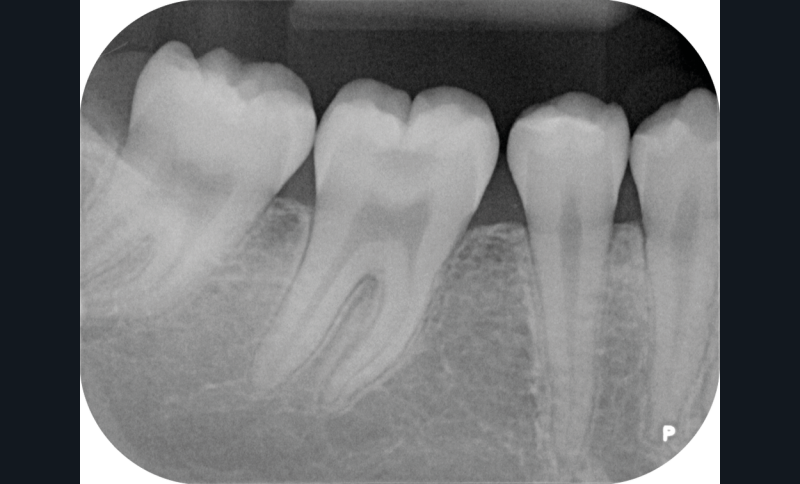

Nous détaillons la technique à travers le cas d’une jeune fille de 18 ans présentant des lésions carieuses sur quatre dents (fig. 1 à 14).